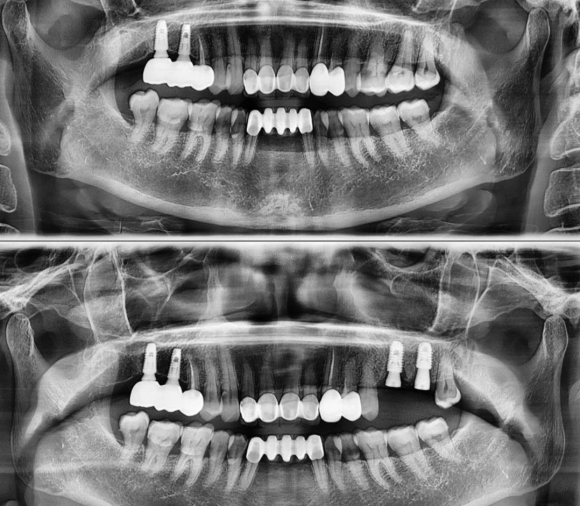

2022.2.28 발치 후 즉시 임플란트 and GBR & sinus lift #상도동에서임플란트가장많이하는치과

2022.2.28 발치 후 즉시 임플란트 and GBR & sinus lift